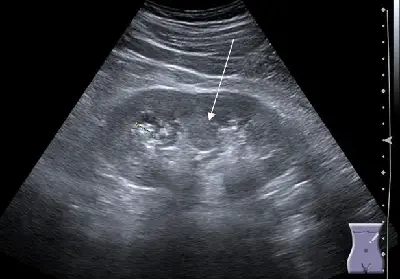

腹部超音波掃描,附圖中箭號所示最可能為何?

影像為腎臟的灰階腹部超音波。腎臟整體輪廓清晰,中央腎竇(renal sinus)呈現高回音。白色箭號指向腎竇偏上極(upper pole)位置的一個類腫塊(mass-like)結構:該結構回音與周圍腎皮質相同(等回音,isoechoic),自腎皮質向腎竇內延伸,造成腎竇高回音區域被類皮質組織「劈開」的外觀,有學者稱為「分裂腎竇徵(split sinus sign)」。此結構邊界清楚但不規則,無明顯後增強或聲影,整體回音均勻,與正常腎皮質無法區分。這些超音波特徵高度符合 Bertin 柱肥厚。影像中無可見強回音伴後方聲影的結石,亦無明顯低回音腫塊、腎表面波浪狀輪廓或血管瘤樣表現。

(A) hypertrophic column of Bertin(Bertin 柱肥厚) 超音波表現:等回音於腎皮質、自皮質延伸入腎竇、邊界清楚、無明顯佔位效應、造成腎竇回音劈裂(split sinus sign)。